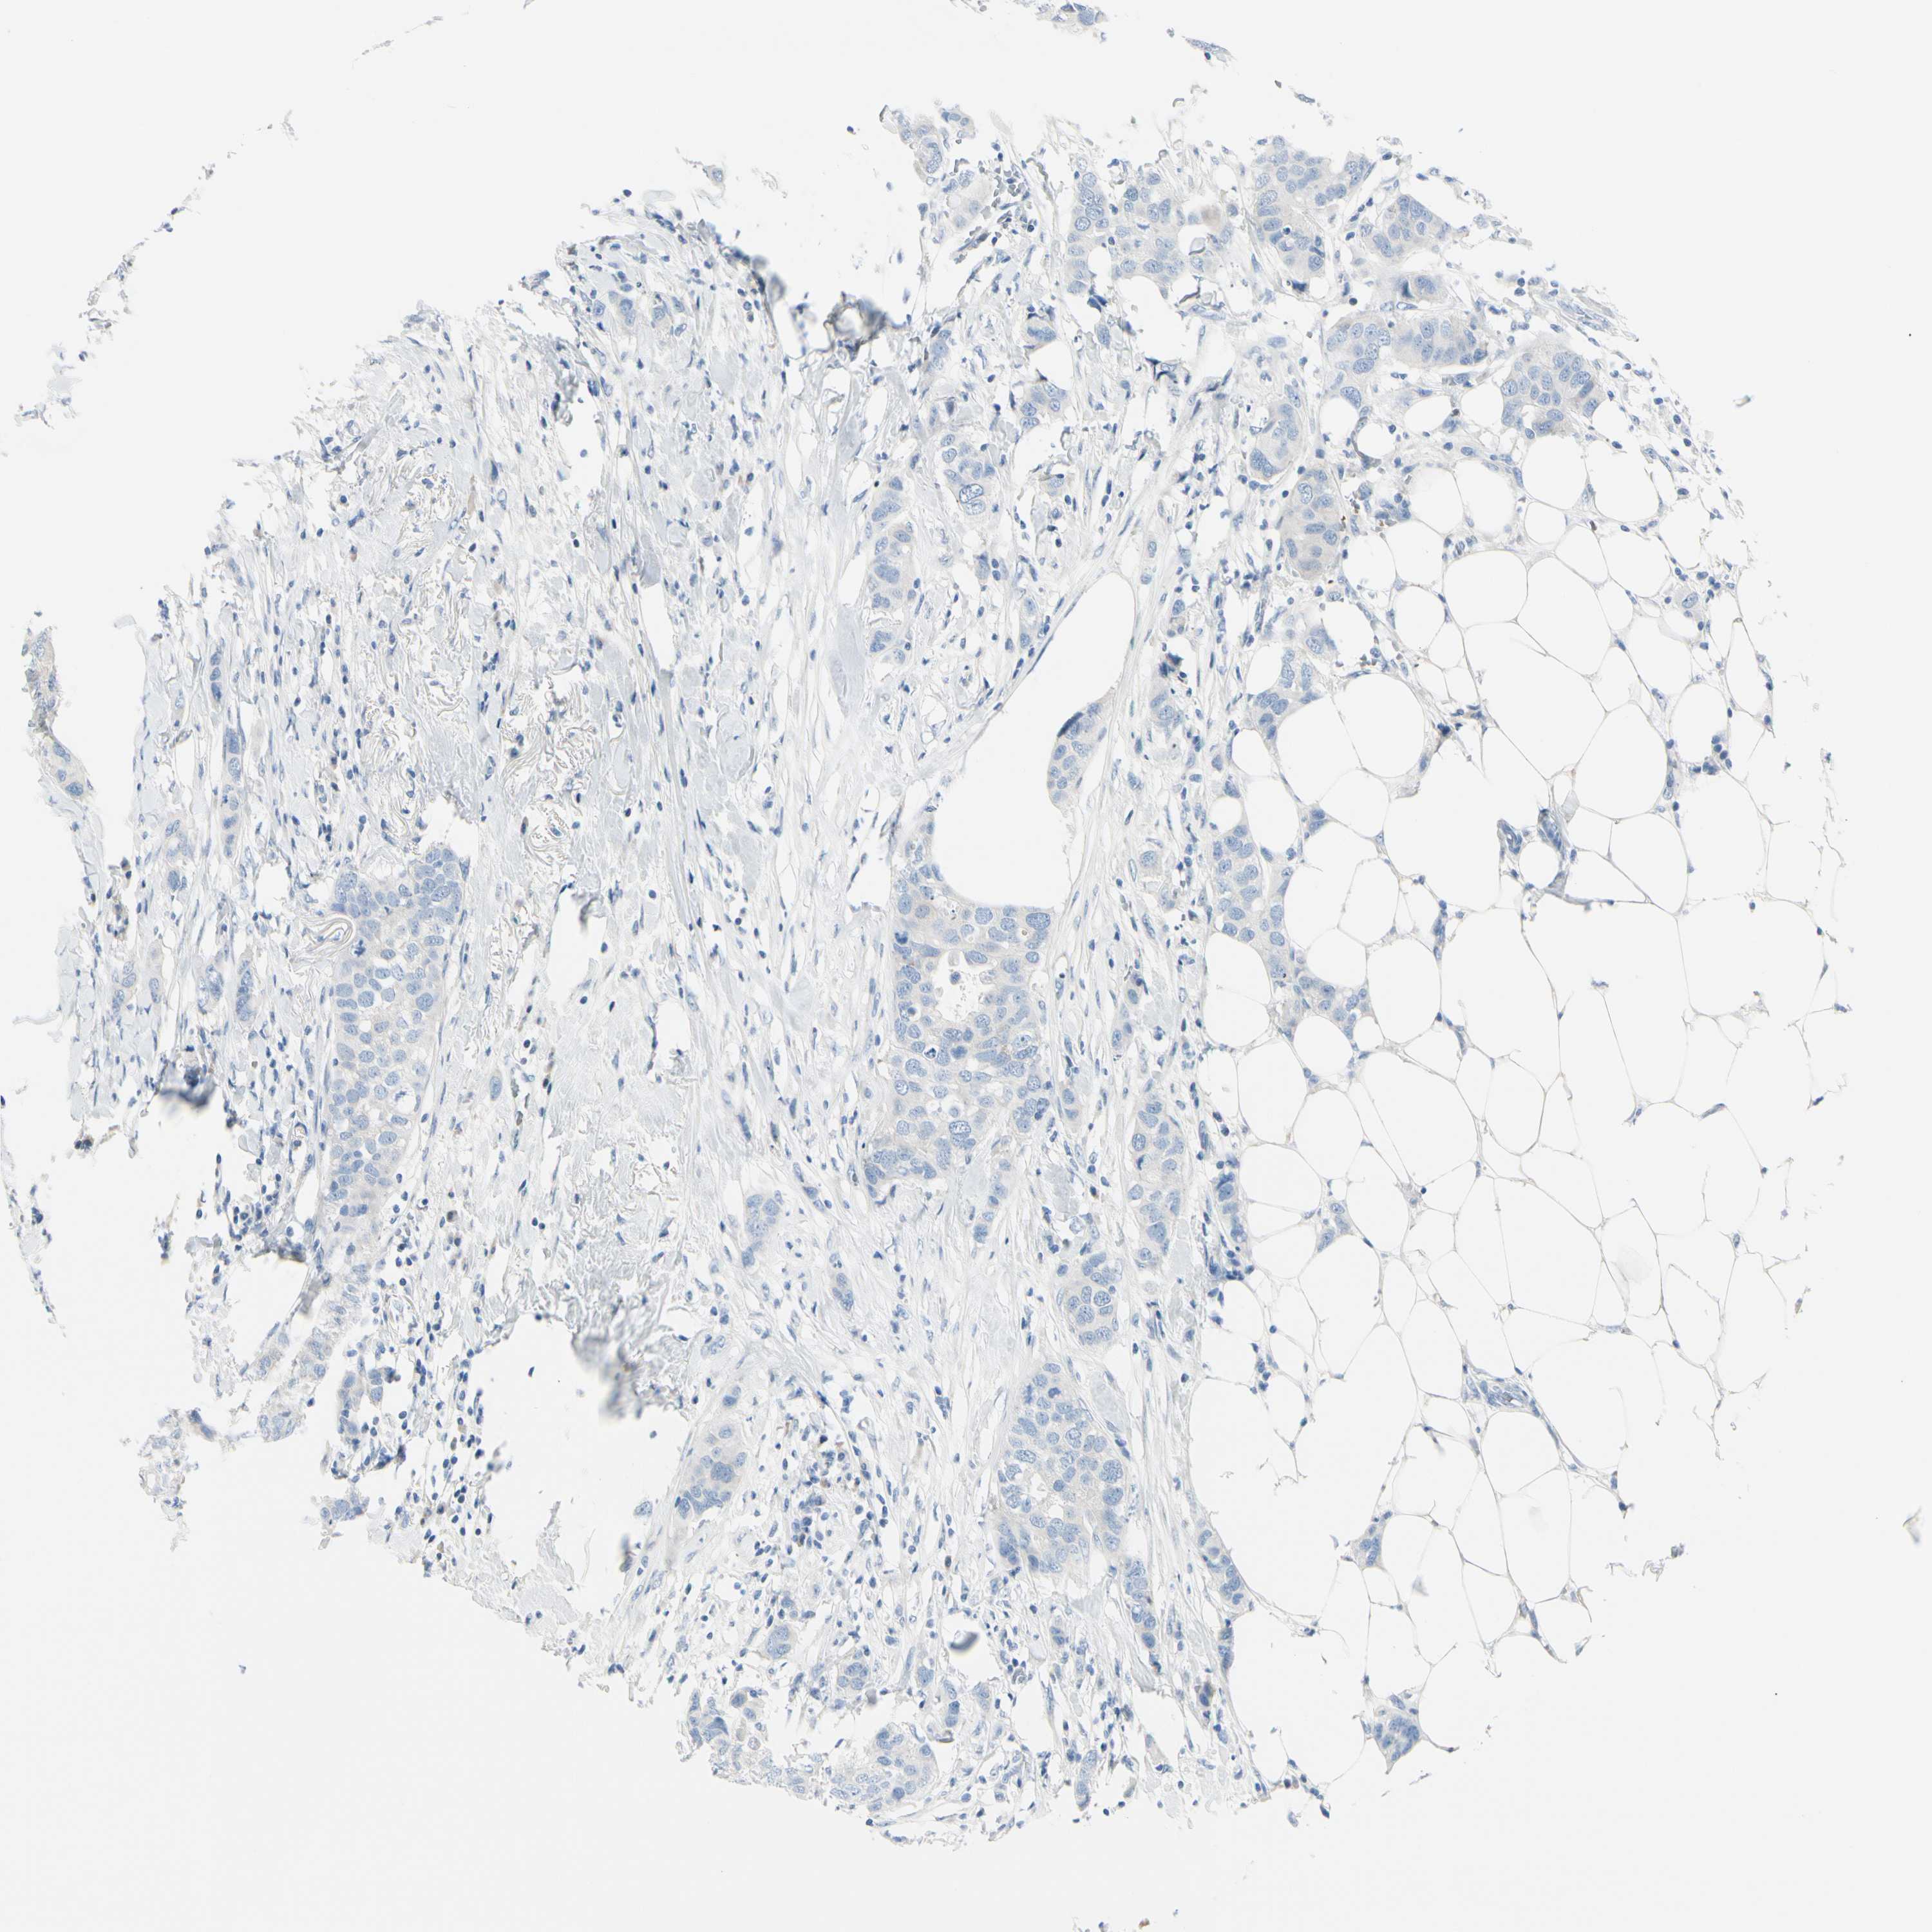

CANCER BREAST CANCER Show tissue menu

BRCA TCGA BRCA VALIDATION PROTEIN EXPRESSION

Breast cancer

Human cancer